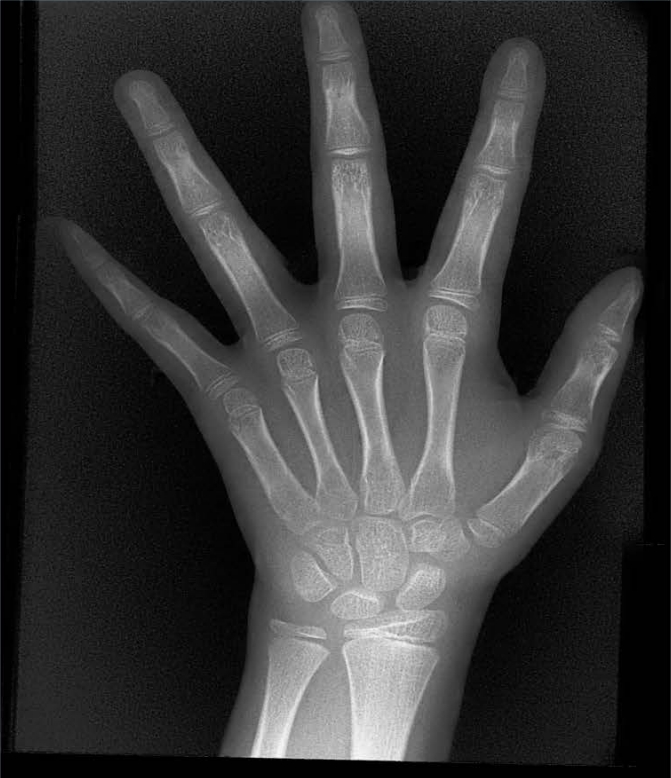

X射線骨齡儀通過拍攝兒童手腕部(指骨、掌骨、腕骨)的X射線影像,依據(jù)骨骼的形態(tài)、大小、鈣化程度等特征,結合評估標準(如《中國青少年兒童手腕骨成熟度及評價方法》,簡稱《中華-05》標準)進行骨齡判定。相較于傳統(tǒng)檢測方式,X射線骨齡儀具有輻射劑量低、影像清晰度高、檢測效率高的優(yōu)勢,能精準捕捉骨骼發(fā)育的細微變化,為骨齡評估的準確性提供保障。